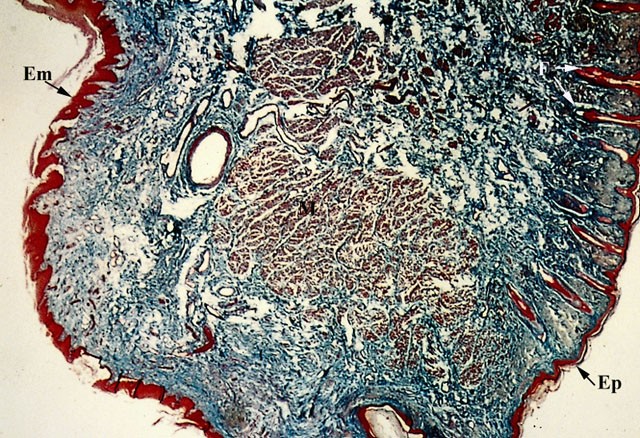

Sezione di labbro umano.

Il labbro è costituito da tre strati: quello superficiale è dato dalla cute, quello intermedio dallo strato muscolare e quello profondo dalla tonaca mucosa.

La cute è formata da epidermide e derma. L’epidermide (Ep) è formata da un epitelio pavimentoso pluristratificato, mentre il derma è ricchissimo di fibre elastiche.

Lo strato muscolare (M) è formato in prevalenza dal muscolo orbicolare della bocca.

La tonaca mucosa è sottile ed è rivestita da un epitelio pavimentoso pluristratificato (Em).